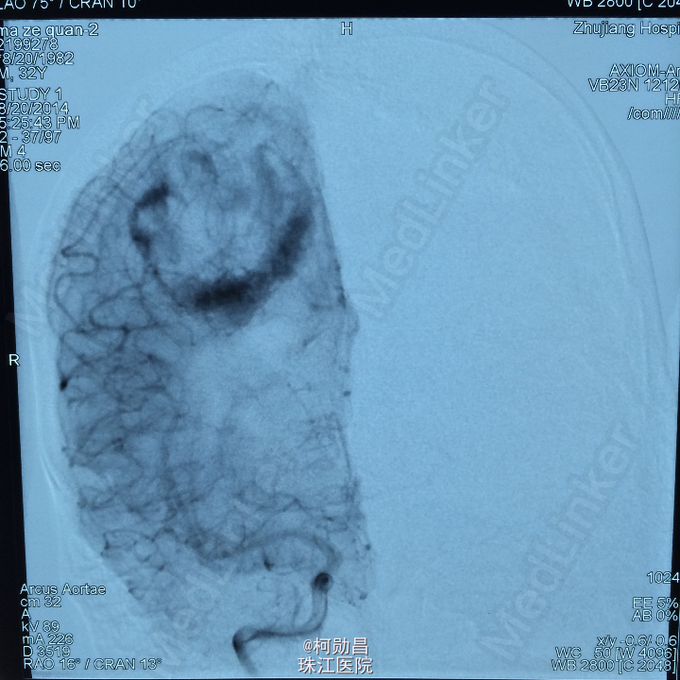

主诉:头痛伴右上肢麻木无力两个月,加重七天 病史:两个月前出现头痛,走路不稳,右上肢无力,不能持物,过去两个月曾有两次癫痫全面发作,发作时意识丧失,但无尿失禁及舌头咬伤。查头MRI示右侧顶叶占位,考虑脑膜瘤。

查体:巴氏征阳性,左侧肢体感觉减退,肌力正常,余无特殊阳性。 辅助检查:查头MRI示右侧顶叶占位,考虑脑膜瘤。

诊断:左侧顶叶占位 处理:行DSA检查,提示肿瘤染色,予PVA颗粒行血管内栓塞治疗。

术后再予开颅手术治疗,书中见供血动脉闭塞,出血量少。